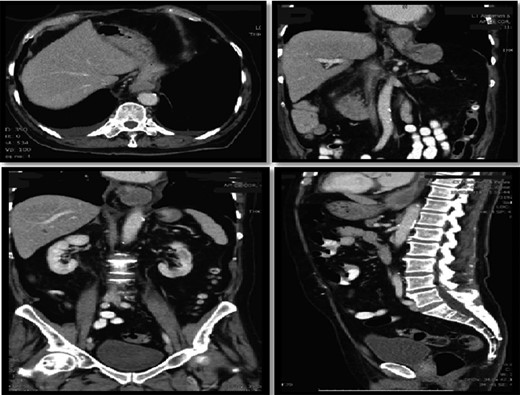

Interval gastroscopy in 2 weeks showed healing mucosal ischemia with slough from 27–30 cm (Fig. 3). Clear fluids were commenced and gradually upgraded to normal diet. Follow-up CT showed no contrast extravasation within posterior mediastinum (Fig. 4) and gastroscopy in 8 weeks showed healed esophagus.

Healing mucosal ischemia from upper, mid and distal esophagus.

CT scan at 2 weeks showing no contrast extravasation in posterior mediastinum.